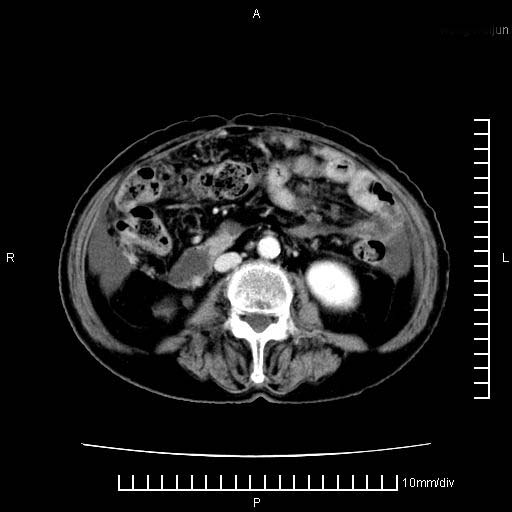

胰腺体部癌累及周围器官,腹膜、粘连

1。胰腺ca伴腹膜腔转移

2。肝左叶低密度灶,考虑转移可能

胰腺体部癌累及周围器官,腹膜、粘连,临床摸到的可能是粘的组织

胰腺结构模糊,胰尾部见囊性包块,周围脂肪密度增高,左肾前筋膜增厚,胸水、腹水。不符合胰腺ca伴腹膜腔转移。考虑胰腺炎伴假性囊肿形成、胸腹腔积液。

1)考虑胰腺癌并胰腺假性囊肿形成。2)肝内低密度灶,不排除转移。3)右肾盂积水。4)腹水。5)右侧胸腔积液并右肺下叶部分膨胀不全。